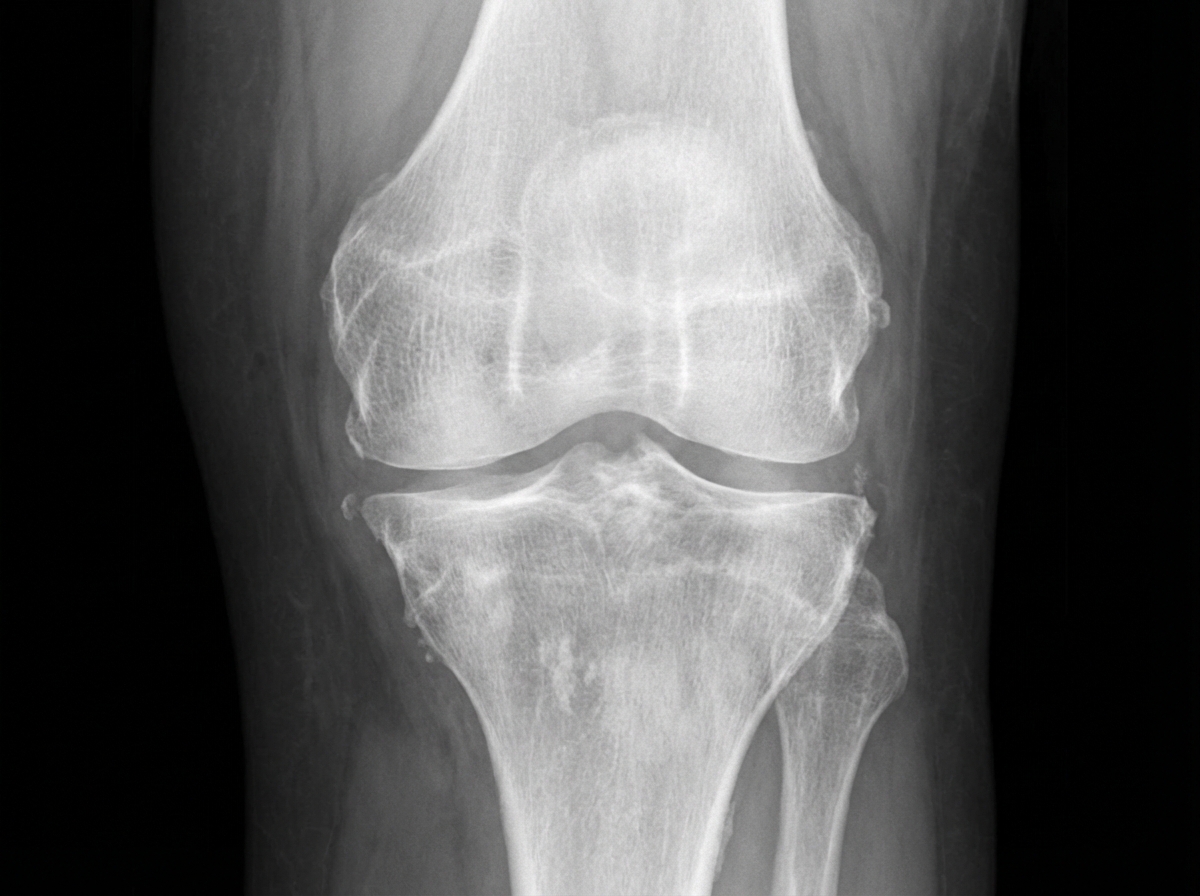

The following X-ray has a feature which is characteristic of which condition?

Explanation: **Explanation:** Hemophilic arthropathy is a chronic joint deformity resulting from recurrent intra-articular bleeding (hemarthrosis). The pathophysiology involves synovial hypertrophy and iron (hemosiderin) deposition, which leads to hypervascularity and cartilage destruction. **Why Option C is correct:** In hemophilic arthropathy of the knee, the **intercondylar notch actually becomes widened (not shortened)**. This occurs because the hypertrophied synovium and chronic inflammation within the notch cause pressure erosion and remodeling of the femoral condyles. **Why the other options are incorrect:** * **A. Patellar squaring:** Chronic hyperemia leads to premature fusion of the growth plates and abnormal remodeling. Squaring of the inferior pole of the patella (Jordan’s sign) is a classic radiological hallmark. * **B. Subchondral cysts:** Recurrent bleeding into the subchondral bone leads to the formation of multiple radiolucent cysts (Geodes), often larger than those seen in osteoarthritis. * **D. Epiphyseal overgrowth:** Increased blood flow (hyperemia) to the joint during the skeletal growth phase causes the epiphyses to enlarge and mature prematurely, often leading to limb length discrepancy. **NEET-PG High-Yield Pearls:** * **Target Joint:** The knee is the most commonly affected joint in hemophilia. * **Arnold-Hilgartner Classification:** Used to stage the severity of hemophilic arthropathy based on X-ray findings. * **MRI:** The gold standard for early detection; it shows **"blooming" artifact** on Gradient Echo (GRE) sequences due to the paramagnetic effect of hemosiderin. * **Differential Diagnosis:** Widened intercondylar notch is also seen in **Juvenile Idiopathic Arthritis (JIA)**, but the presence of dense joint effusions (due to iron) favors hemophilia.

Explanation: ***Osteoarthritis*** - Characteristic X-ray features include **joint space narrowing**, **osteophytes** (bone spurs), **subchondral sclerosis**, and **subchondral cysts**. - Typically affects **weight-bearing joints** like knees and hips, showing asymmetric joint involvement with preserved bone density. *Rheumatoid arthritis* - X-ray shows **symmetric joint involvement** with **periarticular osteopenia** and **joint erosions** at margins. - Features include **joint space narrowing** without osteophytes and **swan neck** or **boutonniere deformities** in hands. *Ankylosing spondylitis* - Characteristic **bamboo spine** appearance with **syndesmophytes** connecting vertebral bodies. - Shows **sacroiliac joint fusion** and **squaring of vertebral bodies**, typically affecting the axial skeleton. *Psoriatic arthritis* - X-ray demonstrates **pencil-in-cup deformity** and **asymmetric joint involvement** with **dactylitis**. - Features include **enthesitis** with bone proliferation and **distal interphalangeal joint** involvement unlike rheumatoid arthritis.

Explanation: **Explanation:** Rheumatoid Arthritis (RA) is a chronic, systemic inflammatory disease primarily characterized by symmetric polyarthritis. The hallmark of RA on imaging is the destruction of joint components due to inflammatory **pannus** formation. **Why "Bone Erosions" is correct:** In RA, the synovial membrane becomes inflamed and hypertrophied (pannus). This pannus releases proteolytic enzymes that digest cartilage and bone. The earliest radiographic changes occur at the **"bare areas"**—regions within the joint capsule where the bone is not covered by protective articular cartilage. These **marginal erosions** are a classic diagnostic feature of RA, typically seen first in the MCP and PIP joints of the hands. **Analysis of Incorrect Options:** * **A. Juxta-articular osteosclerosis:** This is a feature of **Osteoarthritis (OA)**. In RA, the characteristic finding is actually juxta-articular **osteopenia** (decreased bone density) due to increased local blood flow and inflammatory cytokines. * **B. Sacroiliitis:** This is the hallmark of **Seronegative Spondyloarthropathies** (e.g., Ankylosing Spondylitis). RA typically spares the sacroiliac joints and the thoracolumbar spine, though it frequently involves the cervical spine (atlantoaxial subluxation). * **D. Peri-articular calcification:** This is commonly seen in metabolic conditions like **CPPD (Pseudogout)** or Scleroderma, but is not a feature of RA. **High-Yield Clinical Pearls for NEET-PG:** * **Earliest X-ray sign of RA:** Soft tissue swelling. * **Earliest bone sign:** Juxta-articular osteopenia (rarefaction). * **Classic Hand Findings:** Symmetric joint space narrowing, marginal erosions, and late-stage deformities (Swan neck, Boutonniere, and Ulnar deviation). * **Joints Spared:** RA typically spares the **Distal Interphalangeal (DIP) joints**, which are instead involved in OA and Psoriatic Arthritis.